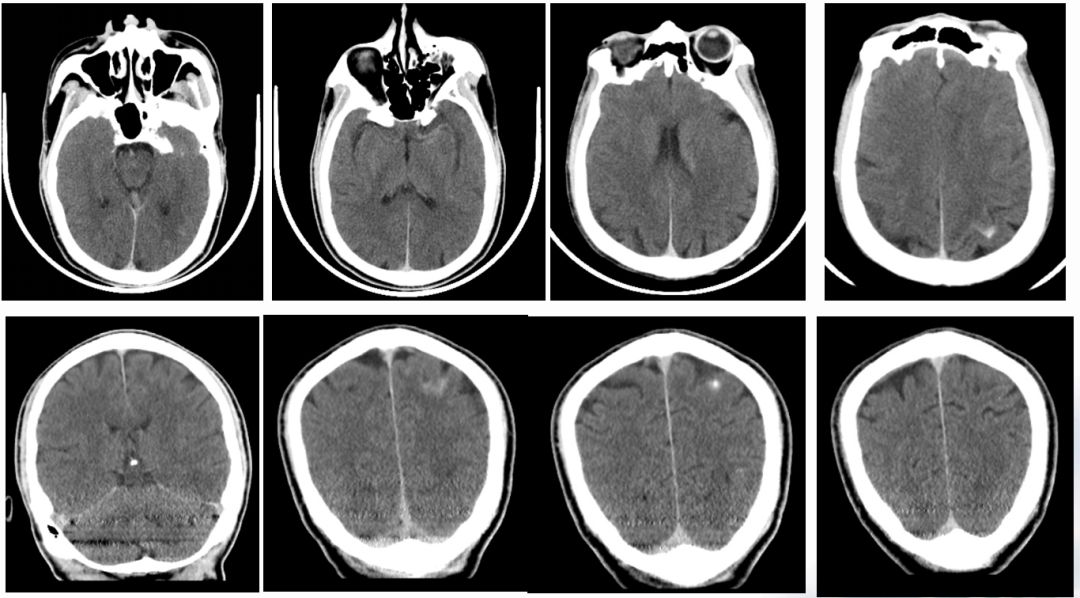

术后即刻CT

术后24h CT

术后第3天,患者突然意识丧失,呼叫无反应,刺激右侧肢体无反应,左侧可见回缩,紧急头颅CT提示左侧半球大量脑出血并破入脑室,很快左侧瞳孔散大,深昏迷,家属拒绝行开颅血肿清除术,自动出院。

术后3天CT:

术后CT

24H

36H

45H